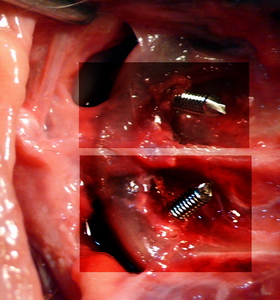

Fijación atlanto axial ventral

Fijación Atlanto Axial agujas roscadas